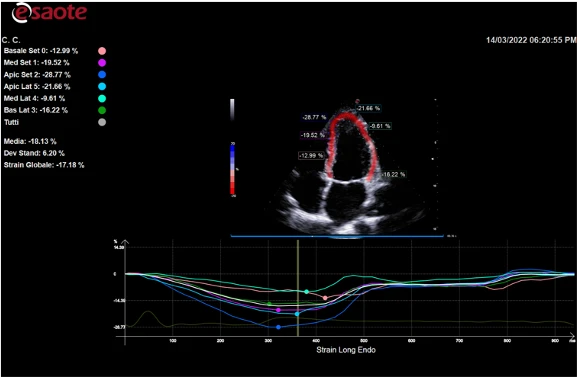

XStrain 2D 3 apikal holatda Bull Eye diagrammasi (17 segment) bilan global chap qorincha kuchlanishini (GLS) tahlil qilish texnologiyasidir.

XStrain4D - yurak faoliyatining hajmli modelini va Bull Eye diagrammasi ko'rinishidagi global deformatsiyalar tahlili hisobotini yaratishga imkon beruvchi dog'larni kuzatish texnologiyasi.